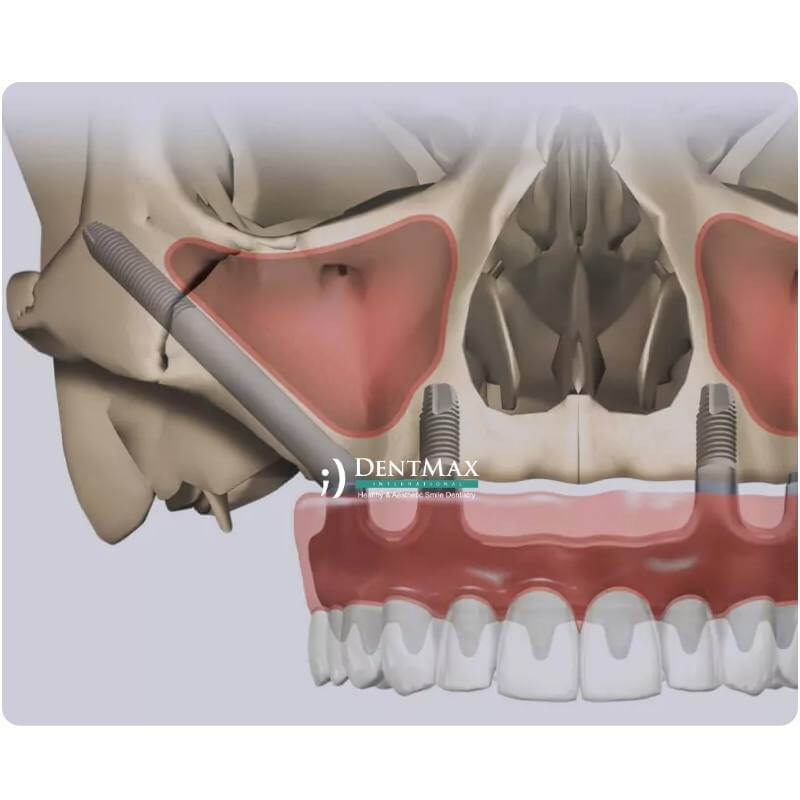

ما هو الزرع الوجني؟ ولمن هو مناسب؟